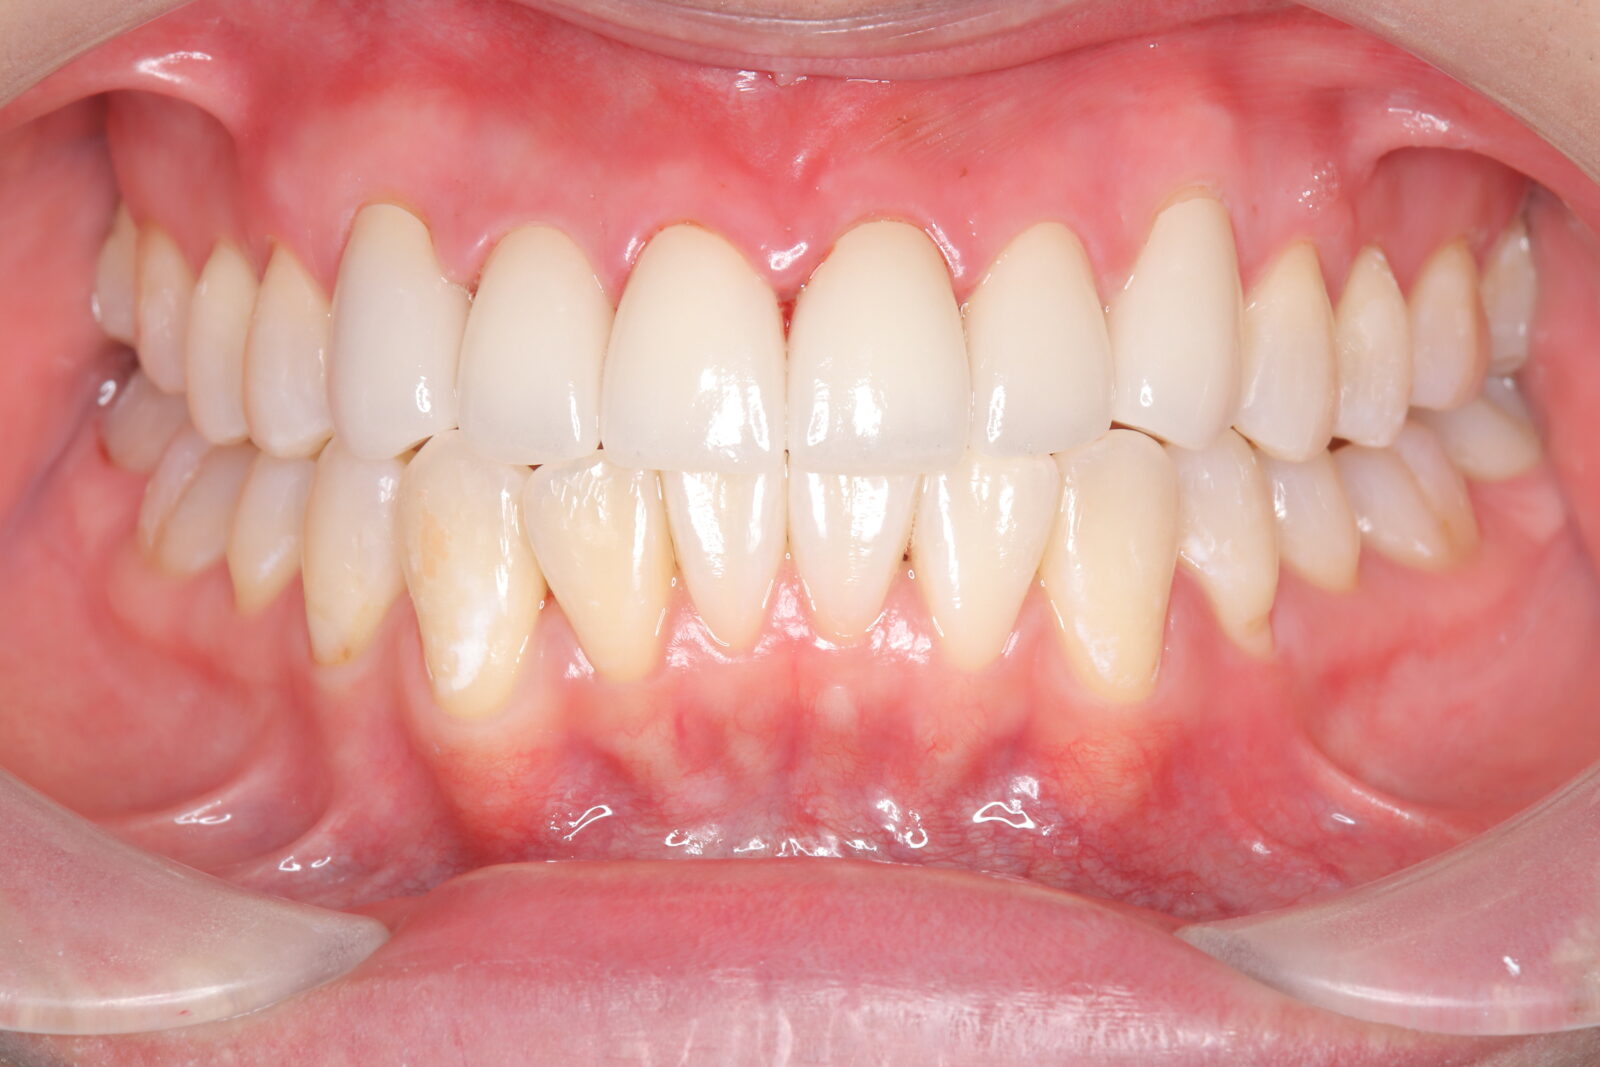

症例紹介

インビザライン(全体矯正)+ホワイトニングコースの症例

コンプレックスだった前歯の歪みと開咬(歯が閉じない状態)をインビザラインで美しく矯正。

・費用:935,000円(税込)

・治療期間:18ヶ月

・通院回数:18回

・32歳女性

-リスクと副作用-

・長時間マウスピースを装着するため、むし歯や歯周病のリスクがある。

・治療後はリテーナーを装着しないと後戻りしてしまうリスクがある。

・ホワイトニング剤の影響で知覚過敏が起こる可能性がある。色が徐々に戻る可能性がる。